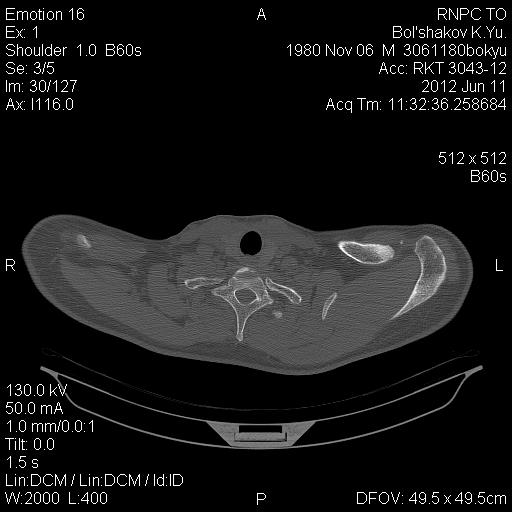

[Ortho] Остеолиз ключицы

Вот как то так выглядят сканыв аксиальной проекции (по отдельности правый и левый суставы) и MPR реконструкция обоих

Имя     : B CT reco hor 0001.jpg

Тип     : image/jpg

Размер  : 37419 байтов

Описание: отсутствует

Url     : http://weborto.net:8080/pipermail/ortho/attachments/20120616/75850712/attachment-0002.jpg